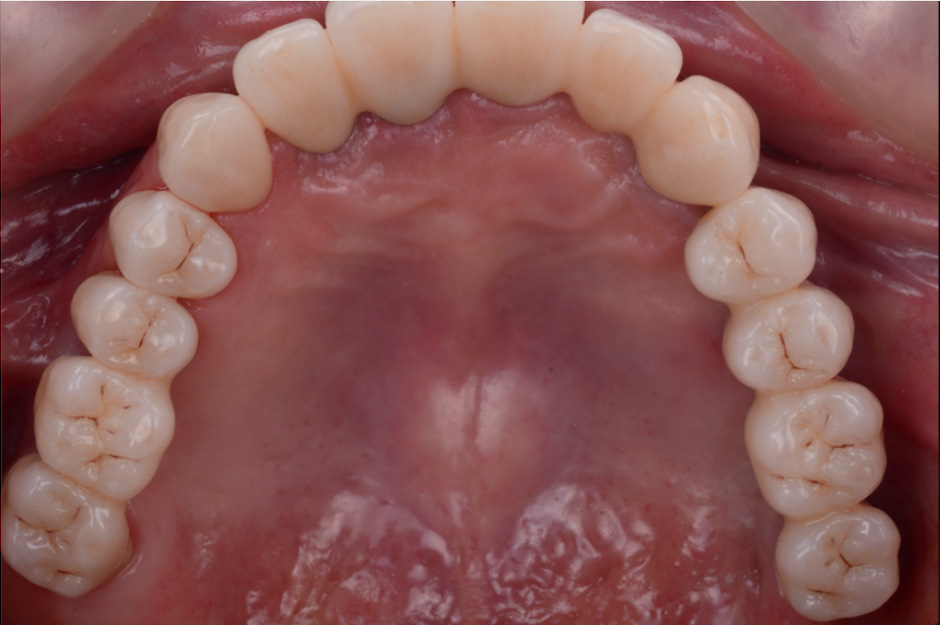

治療前

治療後